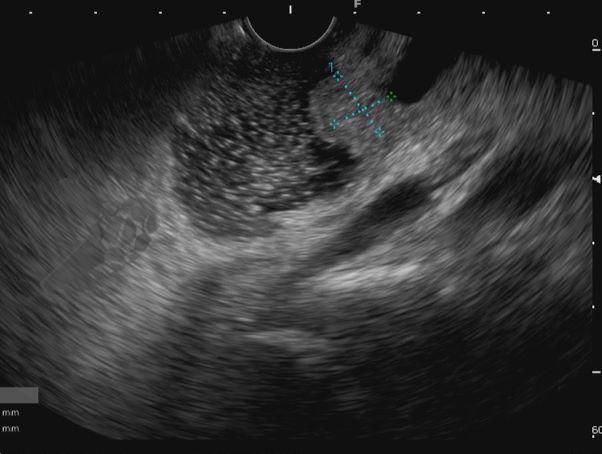

Diante da confirmação histológica de adenoma tubular com displasia de baixo grau, optado pelo estadiamento local através de ultrassom endoscópico (EUS), evidenciando lesão restrita a mucosa (sem sinais de acometimento de camada muscular) medindo 12×9 mm, com dilatação de colédoco até 9 mm e ausência de extensão intraductal.